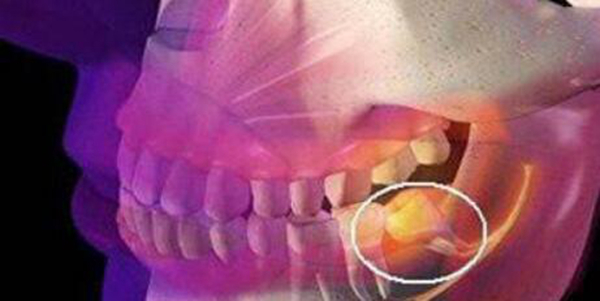

智齿主要指的是人类口腔中的牙槽骨上最里面的第三颗磨牙,有人会长出智齿有人却压根不会,一般都是在以下几种情况下会选择拔牙,一是由于食物残留长出蛀牙,二是长智齿时,一般都会十分疼痛,甚至难以忍受到严重影响正常生活,这时就不得不拔,探秘志带大家共同了解。

而智齿主要指的是人类口腔中的牙槽骨上最里面的第三颗磨牙,有人会在小时候长出来,但是可能在40-50岁长出也有可能,不长也是正常现象,大家都不用感觉到惊慌这些都是正常现象。